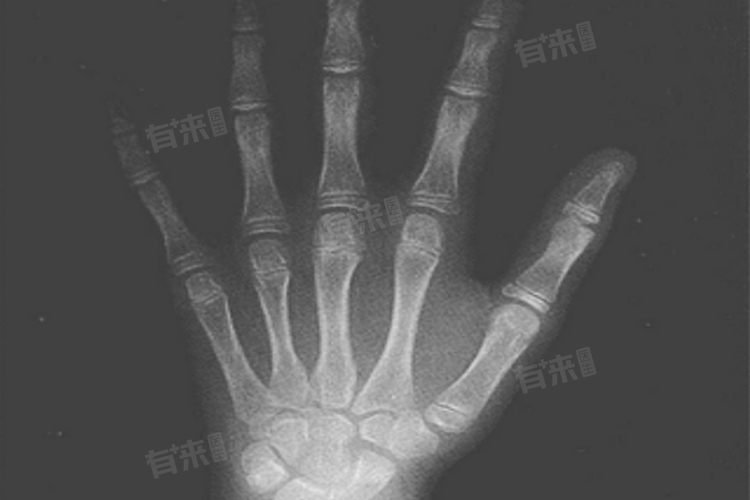

骨龄是指骨骼的成熟程度,通过X光片评估手腕部骨骼的发育情况来确定,骨龄与实际年龄之间的差异可以提供关于儿童生长速度、潜在健康问题以及未来身高预测的重要信息。在决定带孩子去哪个科室进行骨龄检测时,小儿内分泌科和骨科都是可能的选择。